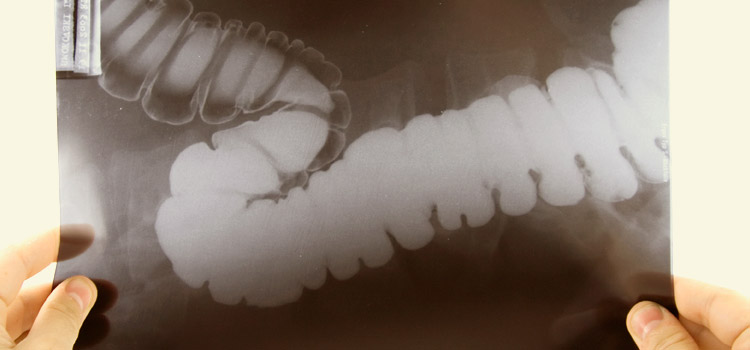

Чем отличается ирригоскопия от колоноскопии? Суть этого вида диагностики кишечника заключается в рентгене, который и просвечивает орган. Для этого кишечник заполняют контрастом — бариевым составом, укладывают пациента на специальный стол и делают снимок. Для чего нужен контраст? Без него ирригографию просто не делают, ведь именно эту жидкость просвечивают рентгеновские лучи во время процедуры. Без контраста снимка – картинки кишечника – просто не увидеть. Подготовка к процедуре ирригоскопии примерно та же, что и в предыдущем случае.

Что дает метод ирригоскопии пациенту? Снимок кишечника дает полное представление анатомии пациента в этой части тела. Здесь можно увидеть, насколько сильно завиты те или иные отделы кишечника, а ведь нередко именно это становится причиной болей пациента после еды. Здесь можно увидеть сужения и расширения в разных сегментах кишечника, что дает возможность врачу предположить наличие патологий.